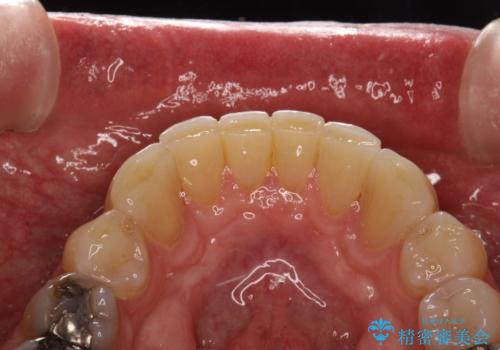

- 歯と歯の間の歯石が気になるとのことで来院されました。PMTC30分コースを行いました。プラークコントロールも悪かったため、歯ブラシ指導も行いました。

プラークが放置されると、そこで病原菌が繁殖し始めます。そうなるとバイオフィルム(歯面に強固に付着したばい菌の膜)になり、歯肉に炎症が生じ歯周病の引き金となります。

プラークやバイオフィルムといった細菌などを放置すると歯石となります。歯石になってしまうと歯磨きでは取り除くことができないため、歯科医院にて専門的な機械や材料を使用してクリーニングを受ける必要があります。